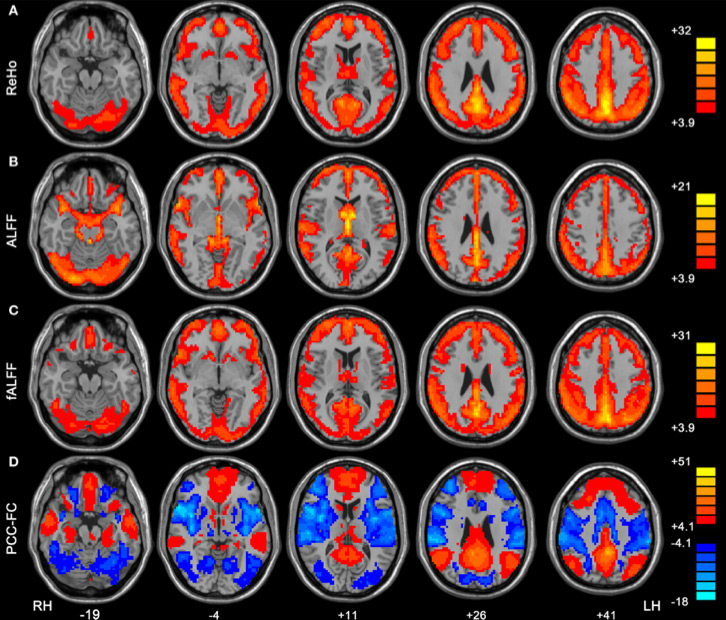

resting-fmri

fMRI in stato di riposo. Aree che si attivano assieme durante la veglia quando il soggetto non è impegnato in nessun compito particolare. Immagine realizzata con un programma elaborato allo State Key Laboratory of Cognitive Neuroscience and Learning della Beijing Normal University.